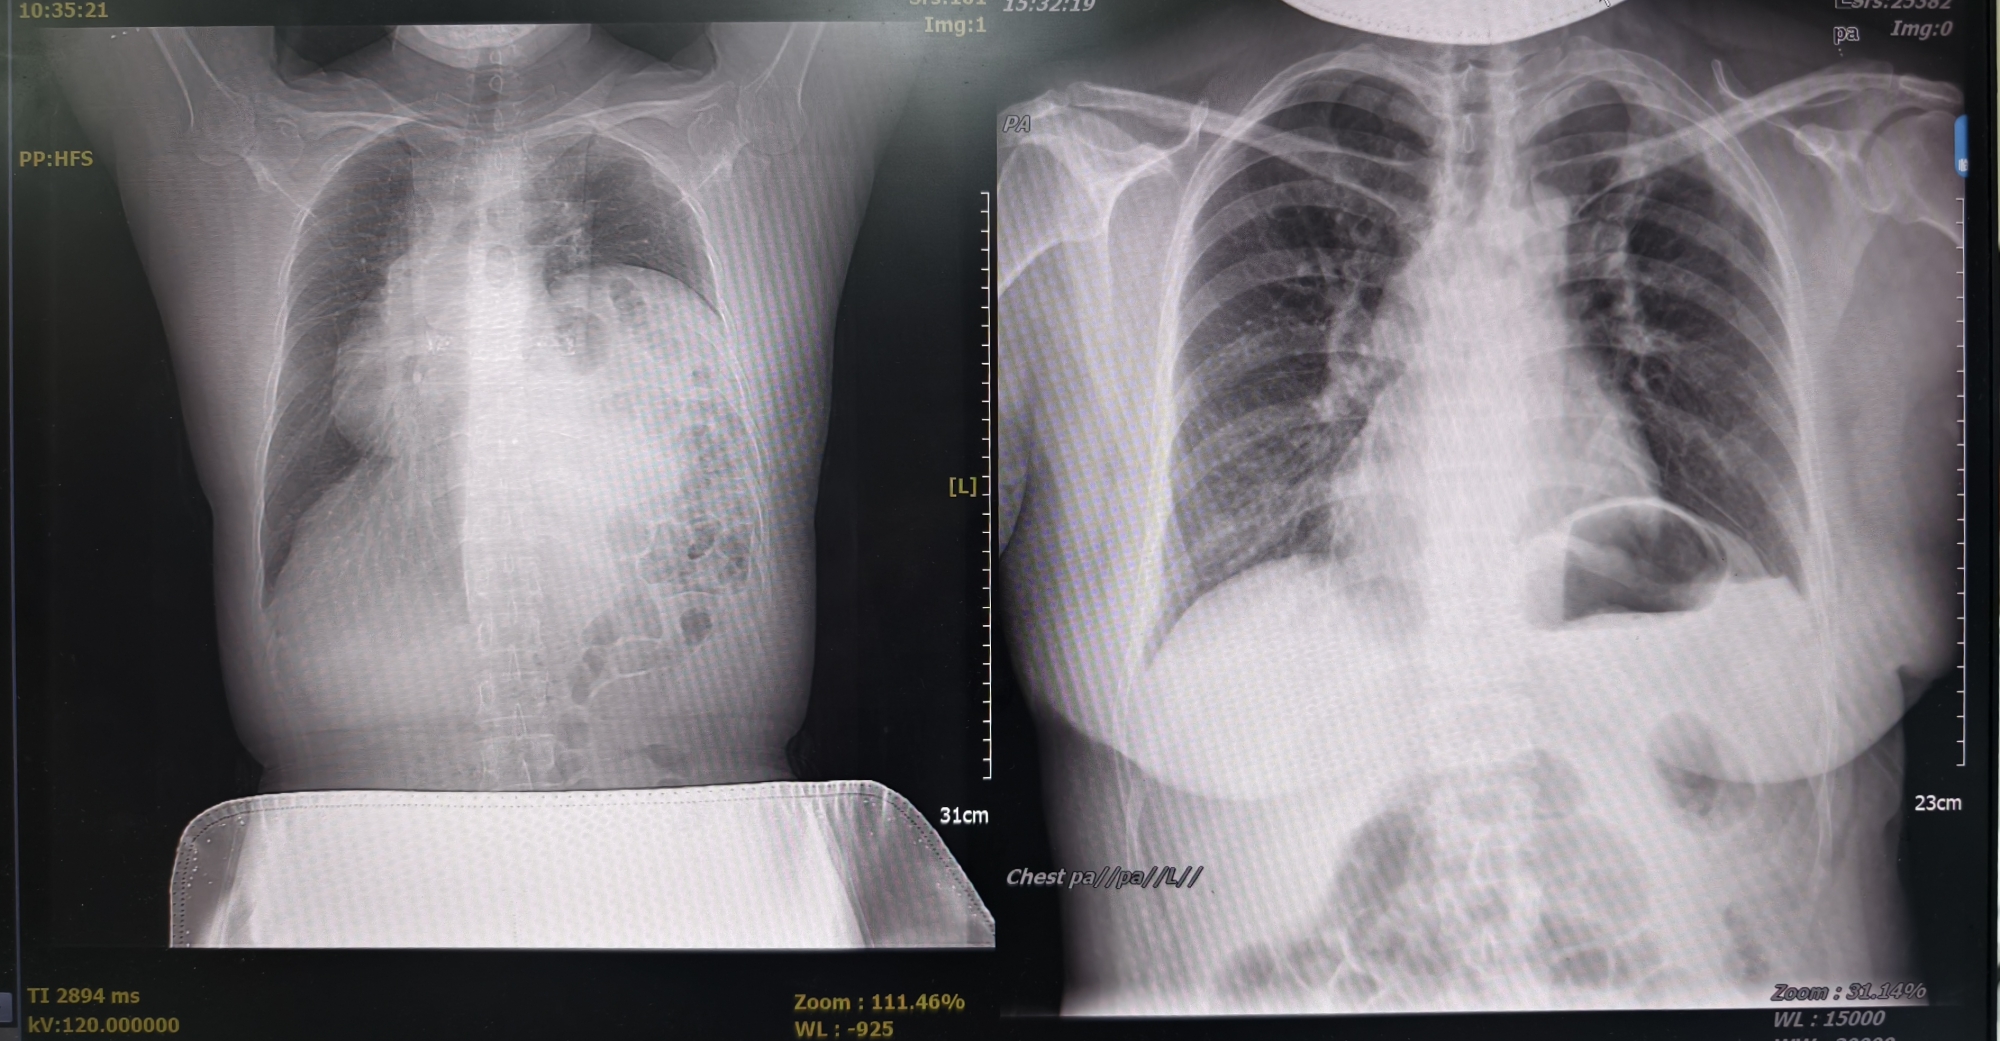

患者贾女士因“进食后腹胀、气促10余天”入院,胸部CT显示:左侧膈肌抬高明显,最高点甚至达到第3-4肋间,左肺及心脏明显受压。膈肌作为人体呼吸的核心肌肉,其异常膨升会压迫腹腔脏器,导致腹胀、呼吸困难甚至心肺功能受损。膈肌折叠手术是治疗膈肌膨升的有效手段,传统手术需开胸进行,创伤大、恢复慢;而常规胸腔镜手术虽属微创,但仍需3-4个操作孔。单孔胸腔镜手术具有创伤最小化(仅需一个操作孔)、术后恢复快、术后并发症少等优势,因此经过胸外科付茂勇教授及施贵冬副教授团队充分的术前评估,最终决定采用目前前沿的“单孔胸腔镜技术”,仅通过左侧腋前线第6肋间一个切口,在高清腔镜引导下完成膈肌折叠手术。整个手术历时80分钟,术中出血50毫升。术后第二天患者即可自主下床活动,自诉胸闷、气促等症状消失,术后三天顺利出院。